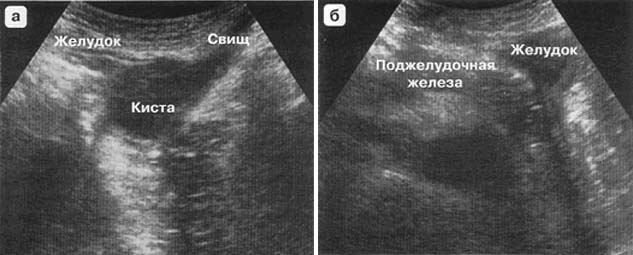

УЗИ диагностика кольцевидной поджелудочной железы: что важно знать